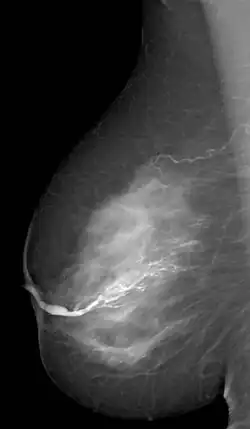

Die Galaktographie (altgriechisch γάλα gála „Milch“ [Genitiv γάλακτος gálaktos] und -graphie) ist ein mammografisches Zusatzverfahren zur Darstellung der Milchgänge. Zu diesem Zweck wird ein wasserlösliches, nichtionisiertes Kontrastmittel mit Hilfe einer Spritze mit Kanüle in den sekretierenden Milchgang gespritzt, eventuell unter lokaler Betäubung. Anschließend werden Röntgenaufnahmen in drei Ebenen angefertigt. Das Untersuchungsergebnis wird als Galaktogramm bezeichnet und stellt Veränderungen innerhalb der Milchgänge dar.

Indikation für eine Galaktographie ist ein blutiges Sekret aus der Brustwarze. Die Galaktografie dient dazu, einen Tumor oder ein Papillom im Milchgang zu entdecken und zu lokalisieren, damit die Veränderung in einer anschließenden Operation entfernt werden kann.